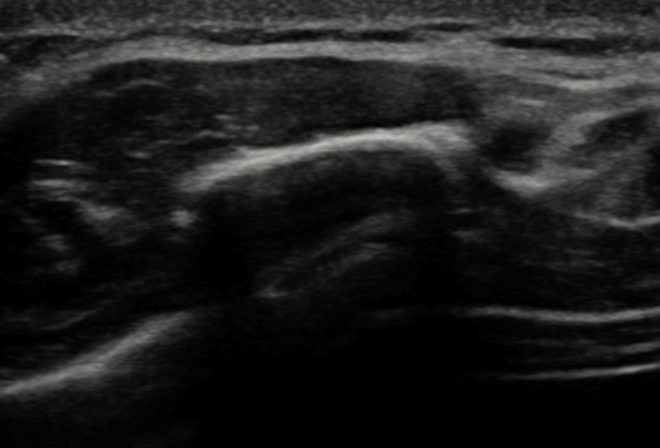

Une échographie a été réalisée au cabinet par Dr Fischhoff montrant : fracture de la jonction chondro-costale au niveau de la 10ème côte.

Dans ce genre de situation, une échographie est beaucoup plus sensible qu’une simple radiographie. Effectivement, les petites fractures de côtes sont très compliquées à voir à la radiographie tandis qu’à l’échographie elles sont visibles ce qui nous permet d’avoir un diagnostic plus précis et donc un traitement plus adapté.